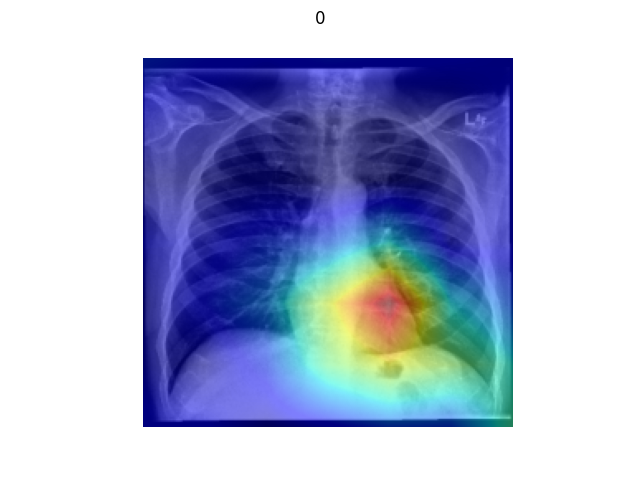

3.2.6. Visual Explanations

As a special test type, visual explanation tools can provide richer information for evaluating the performance of the model than pure error rates. As discussed by (Selvaraju et al., 2017), visual explanations can help users identify error modes, gain trust when establishing and deploying models, and learn more about the model based on its predictions. In Figure 6, we demonstrate several visualizations for Resnet50 on the Chexpert dataset using the Grad-CAM method. The test here is conducted based on the hypothesis that ’perturbation by the basic operators in low contribution regions change the label with low probability AND perturbation by the basic operators in the high contribution regions change the label with high probability.’ With this hypothesis, users can evaluate the correctness of the prediction using their subjective cognition of semantic meaning.

The datasets we use to generate test cases are from the Chexpert paper (Irvin et al., 2019) and the Camelyon17 challenge (Litjens et al., 2018). As shown in Figure 16 and 17, the models are very sensitive to test cases generated by the central occlude operation. This supports the hypothesis that central regions are important regions for the semantic label, especially for some medical imaging datasets. In Figure 18, we conduct visual explanation on the counterfactual analysis. In the counterfactual examples, generated following (Chang et al., 2018), the regions that contribute most to the model’s prediction are blurred with infilling algorithms automatically.